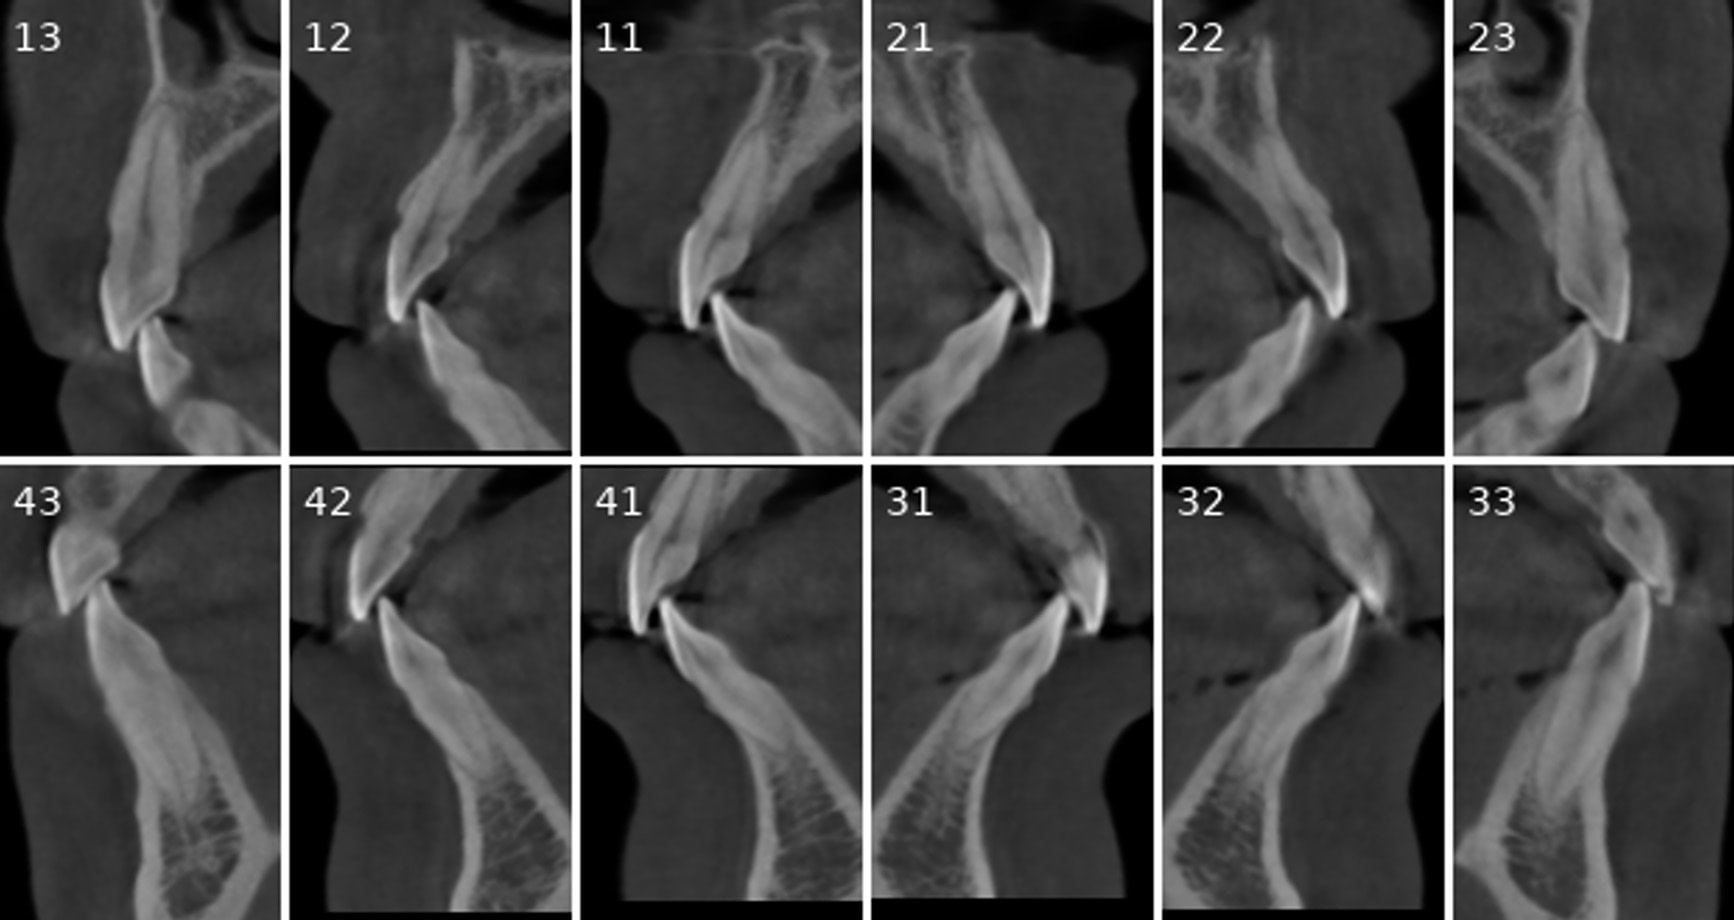

Cross-sectional and coronal views of teeth show torque and buccolingual relationships such as crossbite.

Sagittal and coronal slices and highlighting the angle/curvature/length of the canals.

Measurement of periapical radiolucency volume is a unique advantage with 3D CBCT versus 2D PA. These are endodontic reports for tooth 12 which had a very large periapical radiolucency. The reports were done before and after a long-term calcium hydroxide dressing.